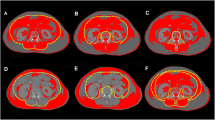

Adipose tissue radiodensity in computed tomography (CT) performed before surgeries can predict surgical difficulty. Despite its clinical importance, little is known about what influences radiodensity. This study combines desorption electrospray ionization mass spectrometry imaging (DESI-MSI) and electrospray ionization (ESI) with machine learning to unveil how chemical composition of adipose tissue determines its radiodensity.

Patients in the study underwent abdominal surgeries. Before surgery, CT radiodensity of fat near operated sites was measured. Fifty-three fat samples were collected and analyzed by DESI-MSI, ESI, and histology, and then sorted by radiodensity, demographic parameters, and adipocyte size. A non-negative matrix factorization (NMF) algorithm was developed to differentiate between high and low radiodensities.

No associations between radiodensity and patient age, gender, weight, height, or fat origin were found. Body mass index showed negative correlation with radiodensity. A substantial difference in chemical composition between adipose tissues of high and low radiodensities was observed. More radiodense tissues exhibited greater abundance of high molecular weight species, such as phospholipids of various types, ceramides, cholesterol esters and diglycerides, and about 70% smaller adipocyte size. Less radiodense tissue showed high abundance of short acyl-tail fatty acids.

This study unveils the connection between abdominal adipose tissue radiodensity and its chemical composition. Because the radiodensity of the fat around the surgical site is associated with surgical difficulty, it is important to understand how adipose tissue composition affects this parameter. We conclude that fat tissue with a higher content of various phospholipids and waxy lipids is more CT radiodense.